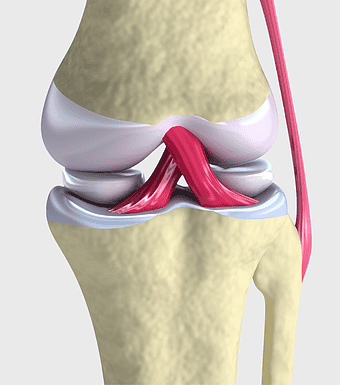

Knee joint illustration, knee replacement surgery, knee pain symptoms, joint replacement therapy, orthopedic graphic design, medical bone structure, arthritis treatment, PNG

- knee joint illustration

- knee replacement surgery

- knee pain symptoms

- joint replacement therapy

- orthopedic graphic design

- medical bone structure

- arthritis treatment

anterior cruciate ligament injury, knee joint anatomy, medial collateral ligament, cruciate ligament tears, knee cartilage damage, joint stabilization techniques, ligament reconstruction surgery -